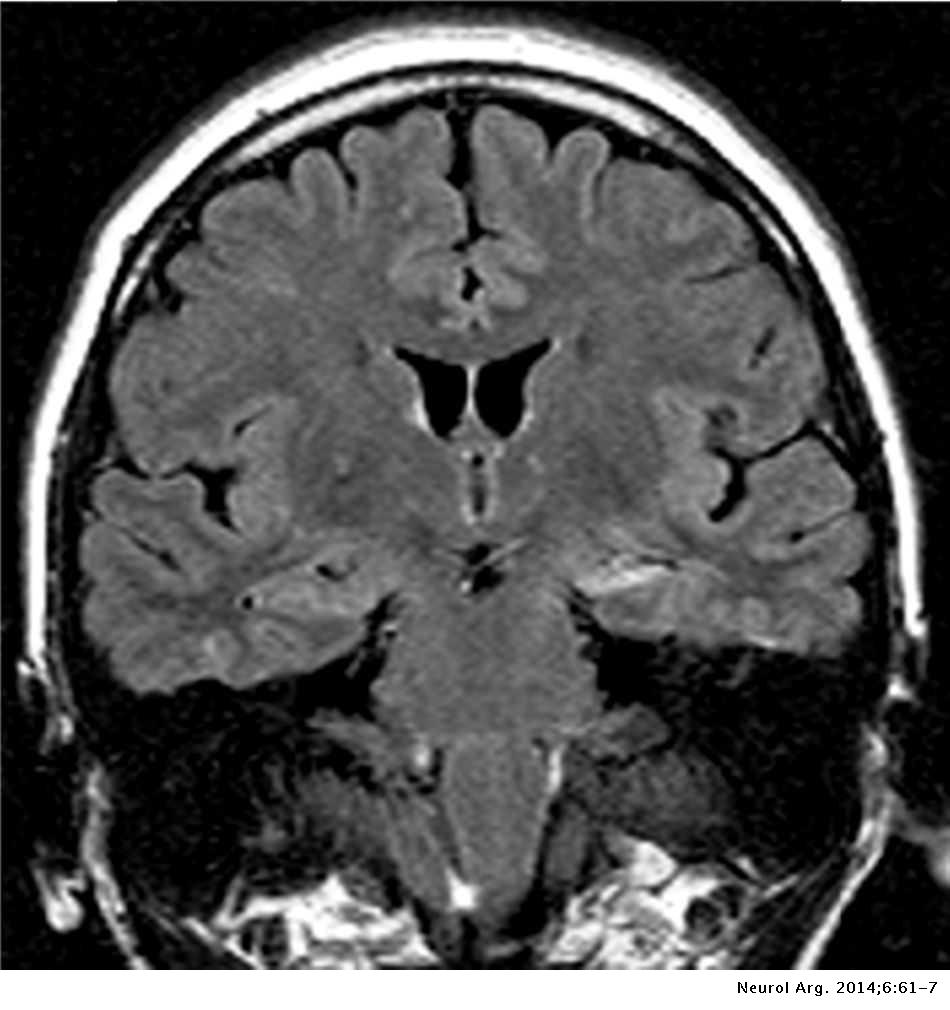

Engineer Team : RESONANCIA MAGNETICA Magnetic Resonance Imaging – Clinical Images Hallazgos por resonancia magnética cerebral de nuestro paciente. M, 21 … Imágenes por resonancia magnética anormales como predictoras de mal … Imágenes por resonancia magnética anormales como predictoras de mal … Lesiones en resonancia magnética (RM) del encéfalo y la médula espinal … Pin en Resonancia Magnética del Encéfalo A) Resonancia magnética cerebral (RMC) mostrando infartos en … Caso 1: Edema cerebral visualizado mediante RM. (A) Secuencia T1 plano … Rascacielos dormir pasta tac y resonancia diferencias retrasar … Pin on Apuntes de Enfermería y T.C.A.E Resonancia magnética cerebral secuencia T2, que muestra lesión … Meningitis aguda en la enfermedad de Behçet | Reumatología Clínica Resonancia magnética coronal normal del cerebro Fotografía de stock – Alamy Imágenes de resonancia magnética, la imagen de la cabeza en diferentes … Resonancia magnética cerebral A) protocolo T1 sagital (Caso 1). Se … Resonancia magnética cerebral. Secuencia T1 corte sagital. Atrofia … Resonancia magnética de cerebro, cortes axiales, secuencias T2. Señal … Resonancia magnética de cráneo. A y B) Cortes axiales FLAIR … Resonancia magnética (RM) de cerebro, corte axial ponderado en T2: la … RM cerebral: Interpretación paso a paso | Kenhub Resonancia magnética de cerebro, cortes axiales, secuencias T2. Señal … De Resonancia Magnética De Cerebro Foto de archivo – Imagen de arteria … Top 107+ Imagenes de resonancia cerebral normal – Destinomexico.mx -Imagen por resonancia magnética del cerebro. a) Cortes sagital y axial … resonanCia magnétiCa Cerebral donde se observa hiperintensidad a nivel … MRI (Imagen de resonancia magnética) – Tomografía computarizada de la … Meningioma – NCI Imágenes por resonancia magnética coloreadas del cerebro sano del … Resonancia magnética cerebral en secuencia FLAIR, que muestra lesiones … Contraste resonancia magnetica cerebral – senturinthegreen Relación de los espacios de Virchow-Robin con la enfermedad de … Gliomatosis cerebral – Instituto Nacional del Cáncer Pin en Neurology. Recomendaciones para la utilización e interpretación de los estudios de … Fotografía De La Proyección De Imagen De Resonancia Magnética Del … atmósfera Dirigir Cumplir anatomia resonancia magnetica Desarrollar … Pin en #MEDICINA,#SALUD Resonancia magnética de la nasofaringe De Resonancia Magnética De Cerebro Foto de archivo – Imagen de polilla … Atrofia cortical global de predominio parietal en la Resonancia … Resonancia magnética cerebral | Download Scientific Diagram Neuroblog: Resonancia magnética cerebral en la trombosis crónica de … De Resonancia Magnética De Cerebro Imagen de archivo – Imagen de … ¿Cuáles son los riesgos de la resonancia magnética? – Integra Salud … Resonancia magnética cerebral al decimocuarto día de ingreso: área … Resonancia magnética. Corte axial mostrando área infartada en el … Resonancia magnética cerebral del paciente AV evidenciando lesiones en … -Ressonância magnética de encéfalo mostrando múltiplas imagens … Resonancia magnética cerebral secuencia FLAIR (Fluid Attenuated … Resonancia magnética cerebral con protocolo de epilepsia, en sección … Resonancia magnética cerebral en corte sagital. Se observa una evidente … Resonancia magnética craneal en la que se evidencian lesiones … Logran visualizar el cerebro a detalle más completo tras una resonancia … Así decide el cerebro la severidad de un castigo De Resonancia Magnética De Cerebro, Imagen de archivo – Imagen de … A) Resonancia magnética cerebral; Secuencia Tof: oclusión de arteria … Un estudio asocia la ansiedad con la aparición rápida del Alzheimer IMÁGENES DE 18 F-PR04.MZ PET FUSIONADA CON RESONANCIA MAGNÉTICA … Imágenes por resonancia magnética anormales como predictoras de mal … Tumores de la región pineal – Instituto Nacional del Cáncer Epilepsia: una historia de voces y fantasmas | Neurología Contribución de las imágenes de resonancia magnética por tensor de … Resonancia magnética secuencia T2 plano coronal de quiste epidermoide … Resonancia Magnética Cerebral del paciente: a. Aumento de… | Download … Resonancia magnética cerebral 2022 Síndrome de hemiconvulsión-hemiplejía-epilepsia. Seguimiento de un caso … Enfoque Radiologico: La resonancia magnética permite detectar lesiones … Resonancia magnética craneal T1 con contraste que muestra angiomatosis … guidewiz – Blog Resonancia magnética cerebral, secuencia SWI. Ribete hipointenso en la … resonAnCiA mAgnétiCA de ColumnA Con gAdolinio. Corte sAgitAl en t1 de … SEMANA 12: FUNDAMENTOS DE RESONANCIA MAGNÉTICA NUCLEAR. INDICACIONES Y … DIAGNÓSTICO DE ESCLEROSIS MÚLTIP Magnetic resonance imaging of the brain – Alchetron, the free social … Resonancia magnética de órbitas | Instituto Radiológico Dr. E Castillo Alteración de la marcha en un paciente post-trasplante hepático Resonancia magnética cerebral de un paciente sano (Ay B) y paciente que … Utilidad de la resonancia magnética craneal para el diagnóstico de la … Resonancia Magnética Del Cerebro El Tumor Cerebral Foto de stock y más … De Resonancia Magnética De Cerebro Imagen de archivo – Imagen de … ABDALLA RADIOLOGIA: NEURINOMA ACUSTICO Atrofia cortical global de predominio parietal en la Resonancia … Resonancia Magnética : Producción de la imagen MRI Brain Scan — Stock Photo © Bunyos30 #18724051 Mri (imagen de resonancia magnética) Monitor con imagen de captura de … Tomografía computarizada vs resonancia magnética: diferencia y … Tumores Cerebrales – Unidad de Neurocirugía RGS Resonancia magnética de la columna, sección sagital. Observe los discos … La resonancia magnética, una técnica imprescindible en el diagnóstico … Perfusión Cerebral por Resonancia Magnética | ¿Qué es? ¿Necesita Contraste? Resonancia Magnética Cerebro A: resonancia magnética, T2 coronal preoperatoria; se observa lesión en … Resonancia magnética cerebral — Foto de stock © Bunyos30 #27340623 La resonancia magnética se perfila como detector de mentiras | Futuro … Resonancia magnética cerebral en T1 con gadolinio, cortes axial (a … MRI brain : show brain tumor at right parietal lobe of cerebrum — Stock … NEUROIMÁGENES EN ENFERMEDAD DE PARKINSON: ROL DE LA RESONANCIA …